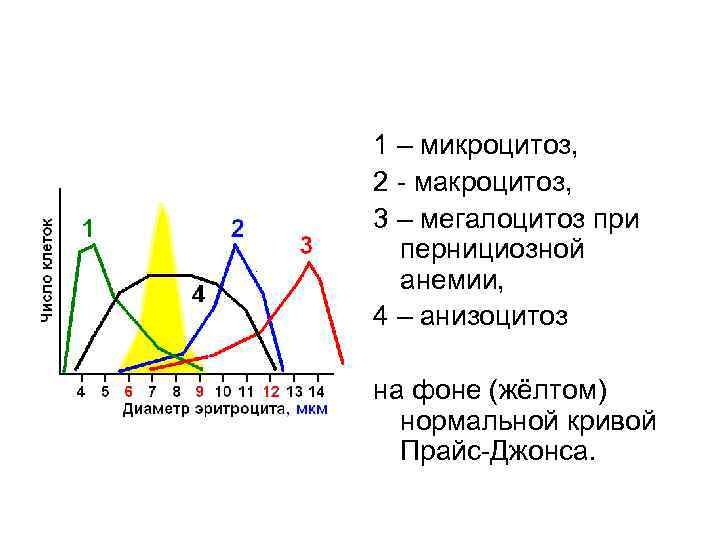

1 – микроцитоз, 2 - макроцитоз, 3 – мегалоцитоз при пернициозной анемии, 4 – анизоцитоз на фоне (жёлтом) нормальной кривой Прайс-Джонса.

1 – микроцитоз, 2 - макроцитоз, 3 – мегалоцитоз при пернициозной анемии, 4 – анизоцитоз на фоне (жёлтом) нормальной кривой Прайс-Джонса.

• При микроцитозе (характерном, например для железодефицитоной анемии) эритроцитометрическая кривая сдвигается влево, кривая становится асимметричной, ширина ее увеличивается. • При макроцитозе (например, сопровождающем В 12 и фолиеводефицитную анемию) кривая Прайс-Джонса сдвигается вправо, уплощается, основание ее расширяется. • Построение кривой Прайс-Джонса вручную - чрезвычайно трудоемкое занятие. • В то же время современные компьютерные системы анализа изображения (например, автоматизированное рабочее место врача-гематолога МЕКОС-Ц 1) быстро и с высокой точностью строят ее в автоматическом режиме. http: //unimedao. ru/hematology. htm

• При микроцитозе (характерном, например для железодефицитоной анемии) эритроцитометрическая кривая сдвигается влево, кривая становится асимметричной, ширина ее увеличивается. • При макроцитозе (например, сопровождающем В 12 и фолиеводефицитную анемию) кривая Прайс-Джонса сдвигается вправо, уплощается, основание ее расширяется. • Построение кривой Прайс-Джонса вручную - чрезвычайно трудоемкое занятие. • В то же время современные компьютерные системы анализа изображения (например, автоматизированное рабочее место врача-гематолога МЕКОС-Ц 1) быстро и с высокой точностью строят ее в автоматическом режиме. http: //unimedao. ru/hematology. htm